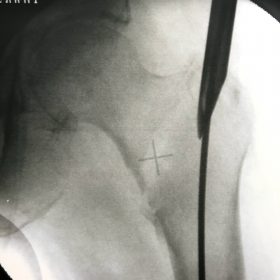

Υποκεφαλικό : Είναι ενδαρθρικό κάταγμα στον αυχένα του μηριαίου (το εσωτερικό του αρθρικού θυλάκου), το οποίο διακόπτει την αιμάτωση της κεφαλής του μηριαίου και οδηγεί σε μη πόρωση του κατάγματος (ΟΣΤΕΟΝΕΚΡΩΣΗ της Μηριαίας κεφαλής). Σε ασθενείς κάτω των 65 ετών αντιμετωπίζεται χειρουργικά με κοχλίωση στις πρώτες 12 ώρες. Τρείς βίδες σε σχήμα Τ με την βοήθεια τηλεόρασης διαδερμικά χωρίς διάνοιξη. Σε ασθενείς από 65-75 ετών γίνεται ολική αρθροπλαστική και σε ασθενείς άνω των 75 ετών αλλάζεται μόνο η κεφαλή χωρίς την αλλαγή της κοτύλης. Ο ασθενής περπατάει άμεσα μετεγχειρητικά στις 5 ώρες και εξέρχεται από το νοσοκομείο σε 1 -2 ημέρες. Στην κοχλίωση μπορεί να εξέλθει και την ίδια ημέρα.